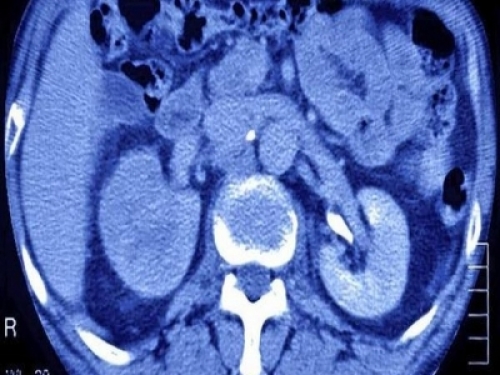

隨著經濟的發展,腎癌的發病率逐漸增加,正逐漸對人們的健康造成危害。但是因為腎癌早期的症狀過於隱匿,不少腎癌的患者容易忽視病情,使癌症拖到晚期才被發現。

中山大學附屬腫瘤醫院泌尿科周芳堅教授在接受家庭醫生線上採訪時表示,在臨床上,早期腎癌一般缺少典型症狀,而更多情況是由於進行體檢時,在B超檢查中發現腎臟的病變。

他還表示,早期腎癌如果通過正確積極的治療,5年生存率可以達到90%以上。那麼,哪些病因會誘發腎癌?腎囊腫會導致腎癌發生嗎?

腎囊腫會轉變為腎癌嗎? 很多腎囊腫患者認為腎長東西以後,會不會慢慢變成癌症呢?在大多數的情況下,不必擔心腎囊腫會惡變為腎癌。據瞭解,腎囊腫都是良性病變居多,絕大多數腎囊腫病人在手術後的病例監測中都被確定為良性病變。 但這也並不是絕對的。目前也有發現一些腎囊腫切片病理表現為癌變的個例。因此,腎囊腫患者雖然不用驚恐癌變,但是也應該小心腎囊腫癌變的可能。據瞭解,若在切片病理檢查中發現囊壁厚而不光滑,囊腫的液體為血性,這就表明提示腎囊腫有惡變的可能。

因此說,腎囊腫一般情況下惡變腎癌可能性小,但也不能完全排除惡變為癌的可能性。建議腎囊腫患者,千萬不要,如有不適情況,應及時到醫院檢查治療。